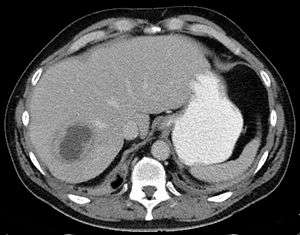

| Liver abscess on axial CT image: a hypodense lesion in the liver with peripherally enhancement. | |

A liver abscess is a pus-filled mass inside the liver.[1] Common causes are abdominal infections such as appendicitis or diverticulitis due to haematogenous spread through the portal vein.[2]